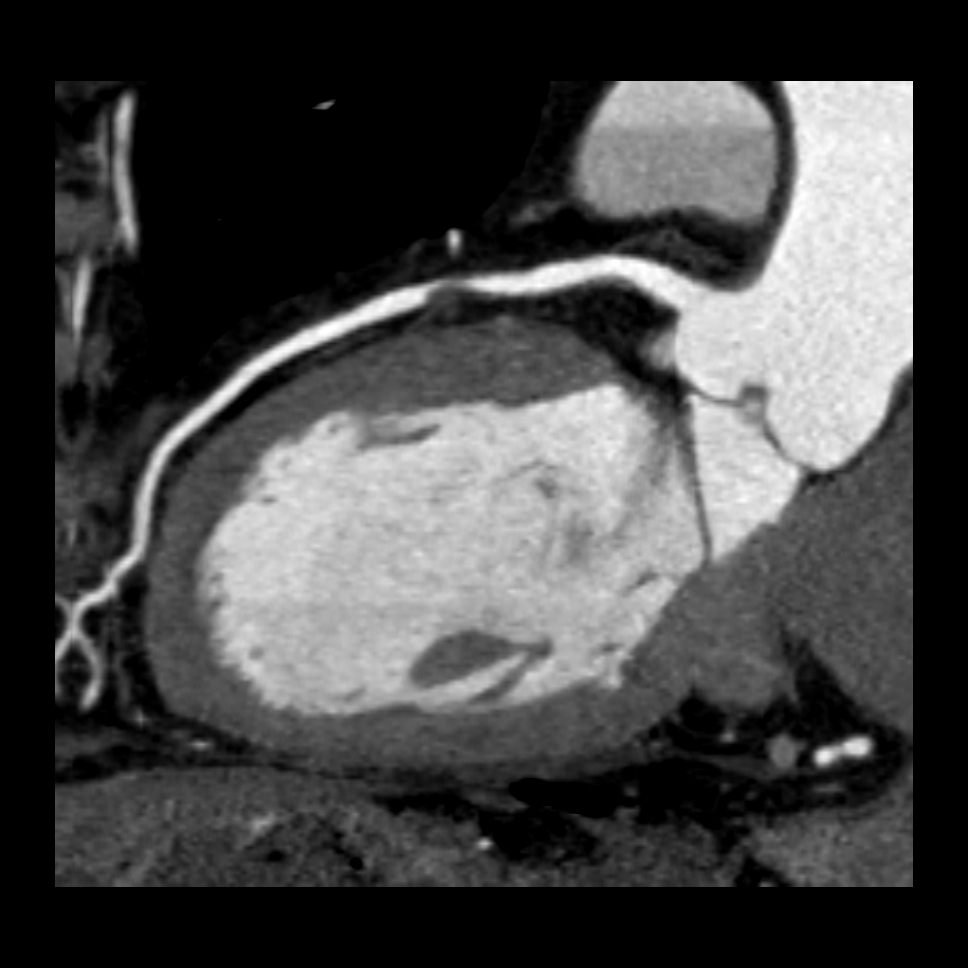

Sie hat sich als eine bedeutende Methode zur nichtinvasiven, das heisst unblutigen Darstellung der Herzkranzgefäße etabliert. Mit Hilfe der CT können bei angemessen ausgewählten und vorbereiteten Patienten mit grosser Zuverlässigkeit Aussagen über das Vorhandensein möglicher Engstellen oder Verschlüsse der Herzkranzgefässe (Abbildung 1), das Ausmass der Herzkranzgefässverkalkungen und die Anatomie des Herzens getroffen werden, und das ohne Herzkatheteruntersuchung. Sind die Herzkranzgefässe bereits erkrankt, so kann unter bestimmten Bedingungen auch eine Darstellung von Bypassgefässen (Abbildung 2) oder Stents erfolgen. Eine blutige Untersuchung mittels Herzkatheter kann somit in vielen Fällen vermieden werden (Abbildung 3). Sollten in der CT relevante Engstellen in einem oder mehreren Koronargefäßen auffallen, muss jedoch meist eine Herzkatheteruntersuchung zur weiterführenden Diagnostik und ggf. Therapie erfolgen.

Abbildung 1: CT – Schnittbild (rechts) sowie dreidimensionale Rekonstruktion (links) zeigen eine hochgradige Engstelle im Bereich der linken Herzkranzarterie.